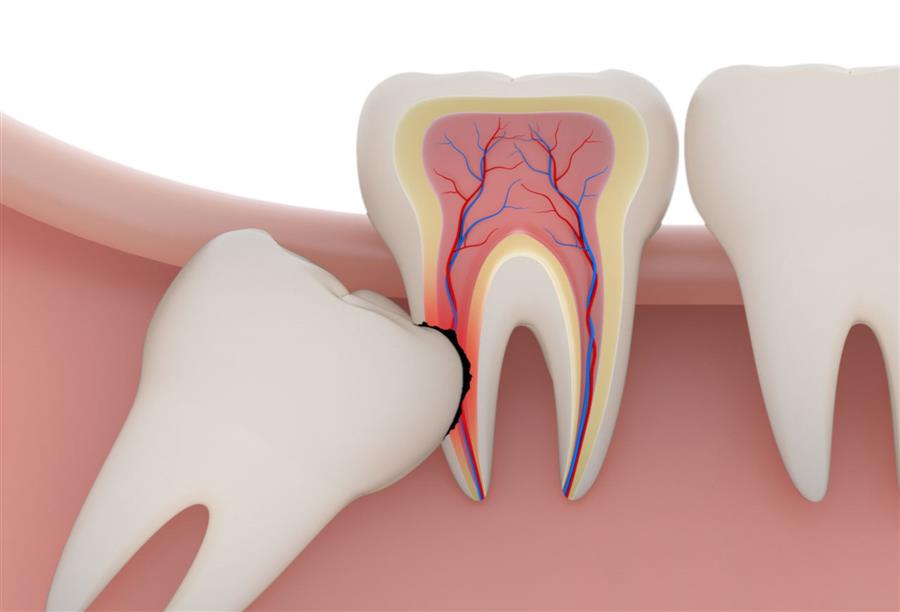

- وأيضا إذا كان الضرس مكسور بدرجة كبيرة ويكون من الصعب التقاطها.

وأضاف أخصائي غرس وتجميل الأسنان، أن عملية خلع ضرس العقل المدفون بنج كامل، وذلك لأن الطبيب يقوم بعمل ثقب في اللثة صغير، وبعد ذلك يزيل جزءا من العظم المحيط بضرس العقل، وذلك حتى يتمكن الطبيب من الوصول إلى الضرس.

وأشار إلى أن الخلع يتم بأدوات جراحة الأسنان التقليدية، وبعد ذلك يقوم الطبيب بعمل خياطة بسيطة مكان الثقب.

وأشار إلى أن الطبيب يأخذ قرار خلع ضرس العقل إذا كان ليس مقابلة ضروس أخرى، الأمر الذي سيكون المضغ فيه غير سليم، وأيضا إذا حدث تسوس وصل إلى مرحلة التهاب الصعب، بالإضافة إذا كان هناك تباين في شكل وعدد القنوات العصبية في ضرس العقل، الأمر الذي يجعل الحشو غير دقيق.